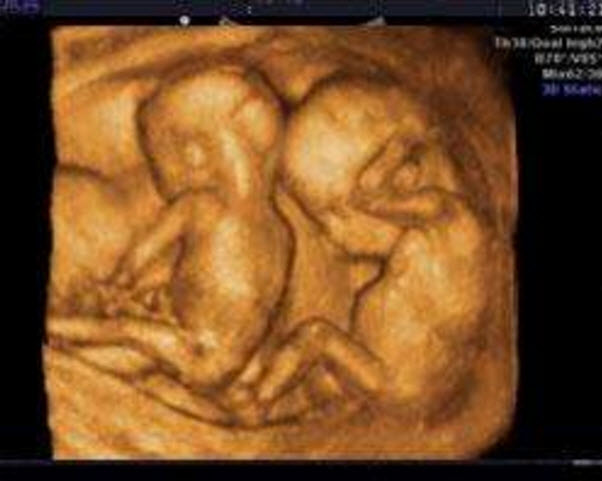

超声波检查检测到两个胎心波

超声波检查检测到两个胎心波是最明显的怀双胞胎的症状 。如果怀了双胞胎 , 那么用超声波检查就可测到两个不同速度的胎心波 , 同时用X线检查也会显示两个胎儿的骨骼 。